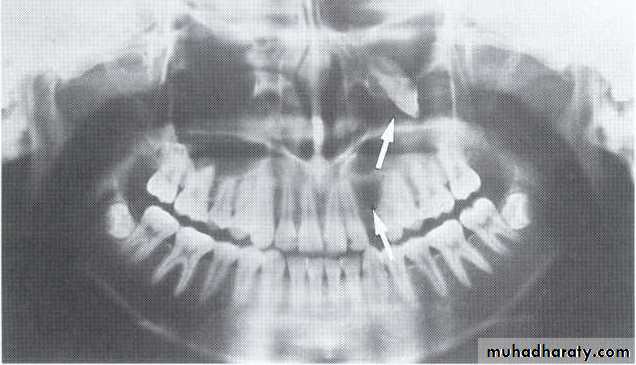

Одонтома нижней челюсти: фотографии и медицинская информация